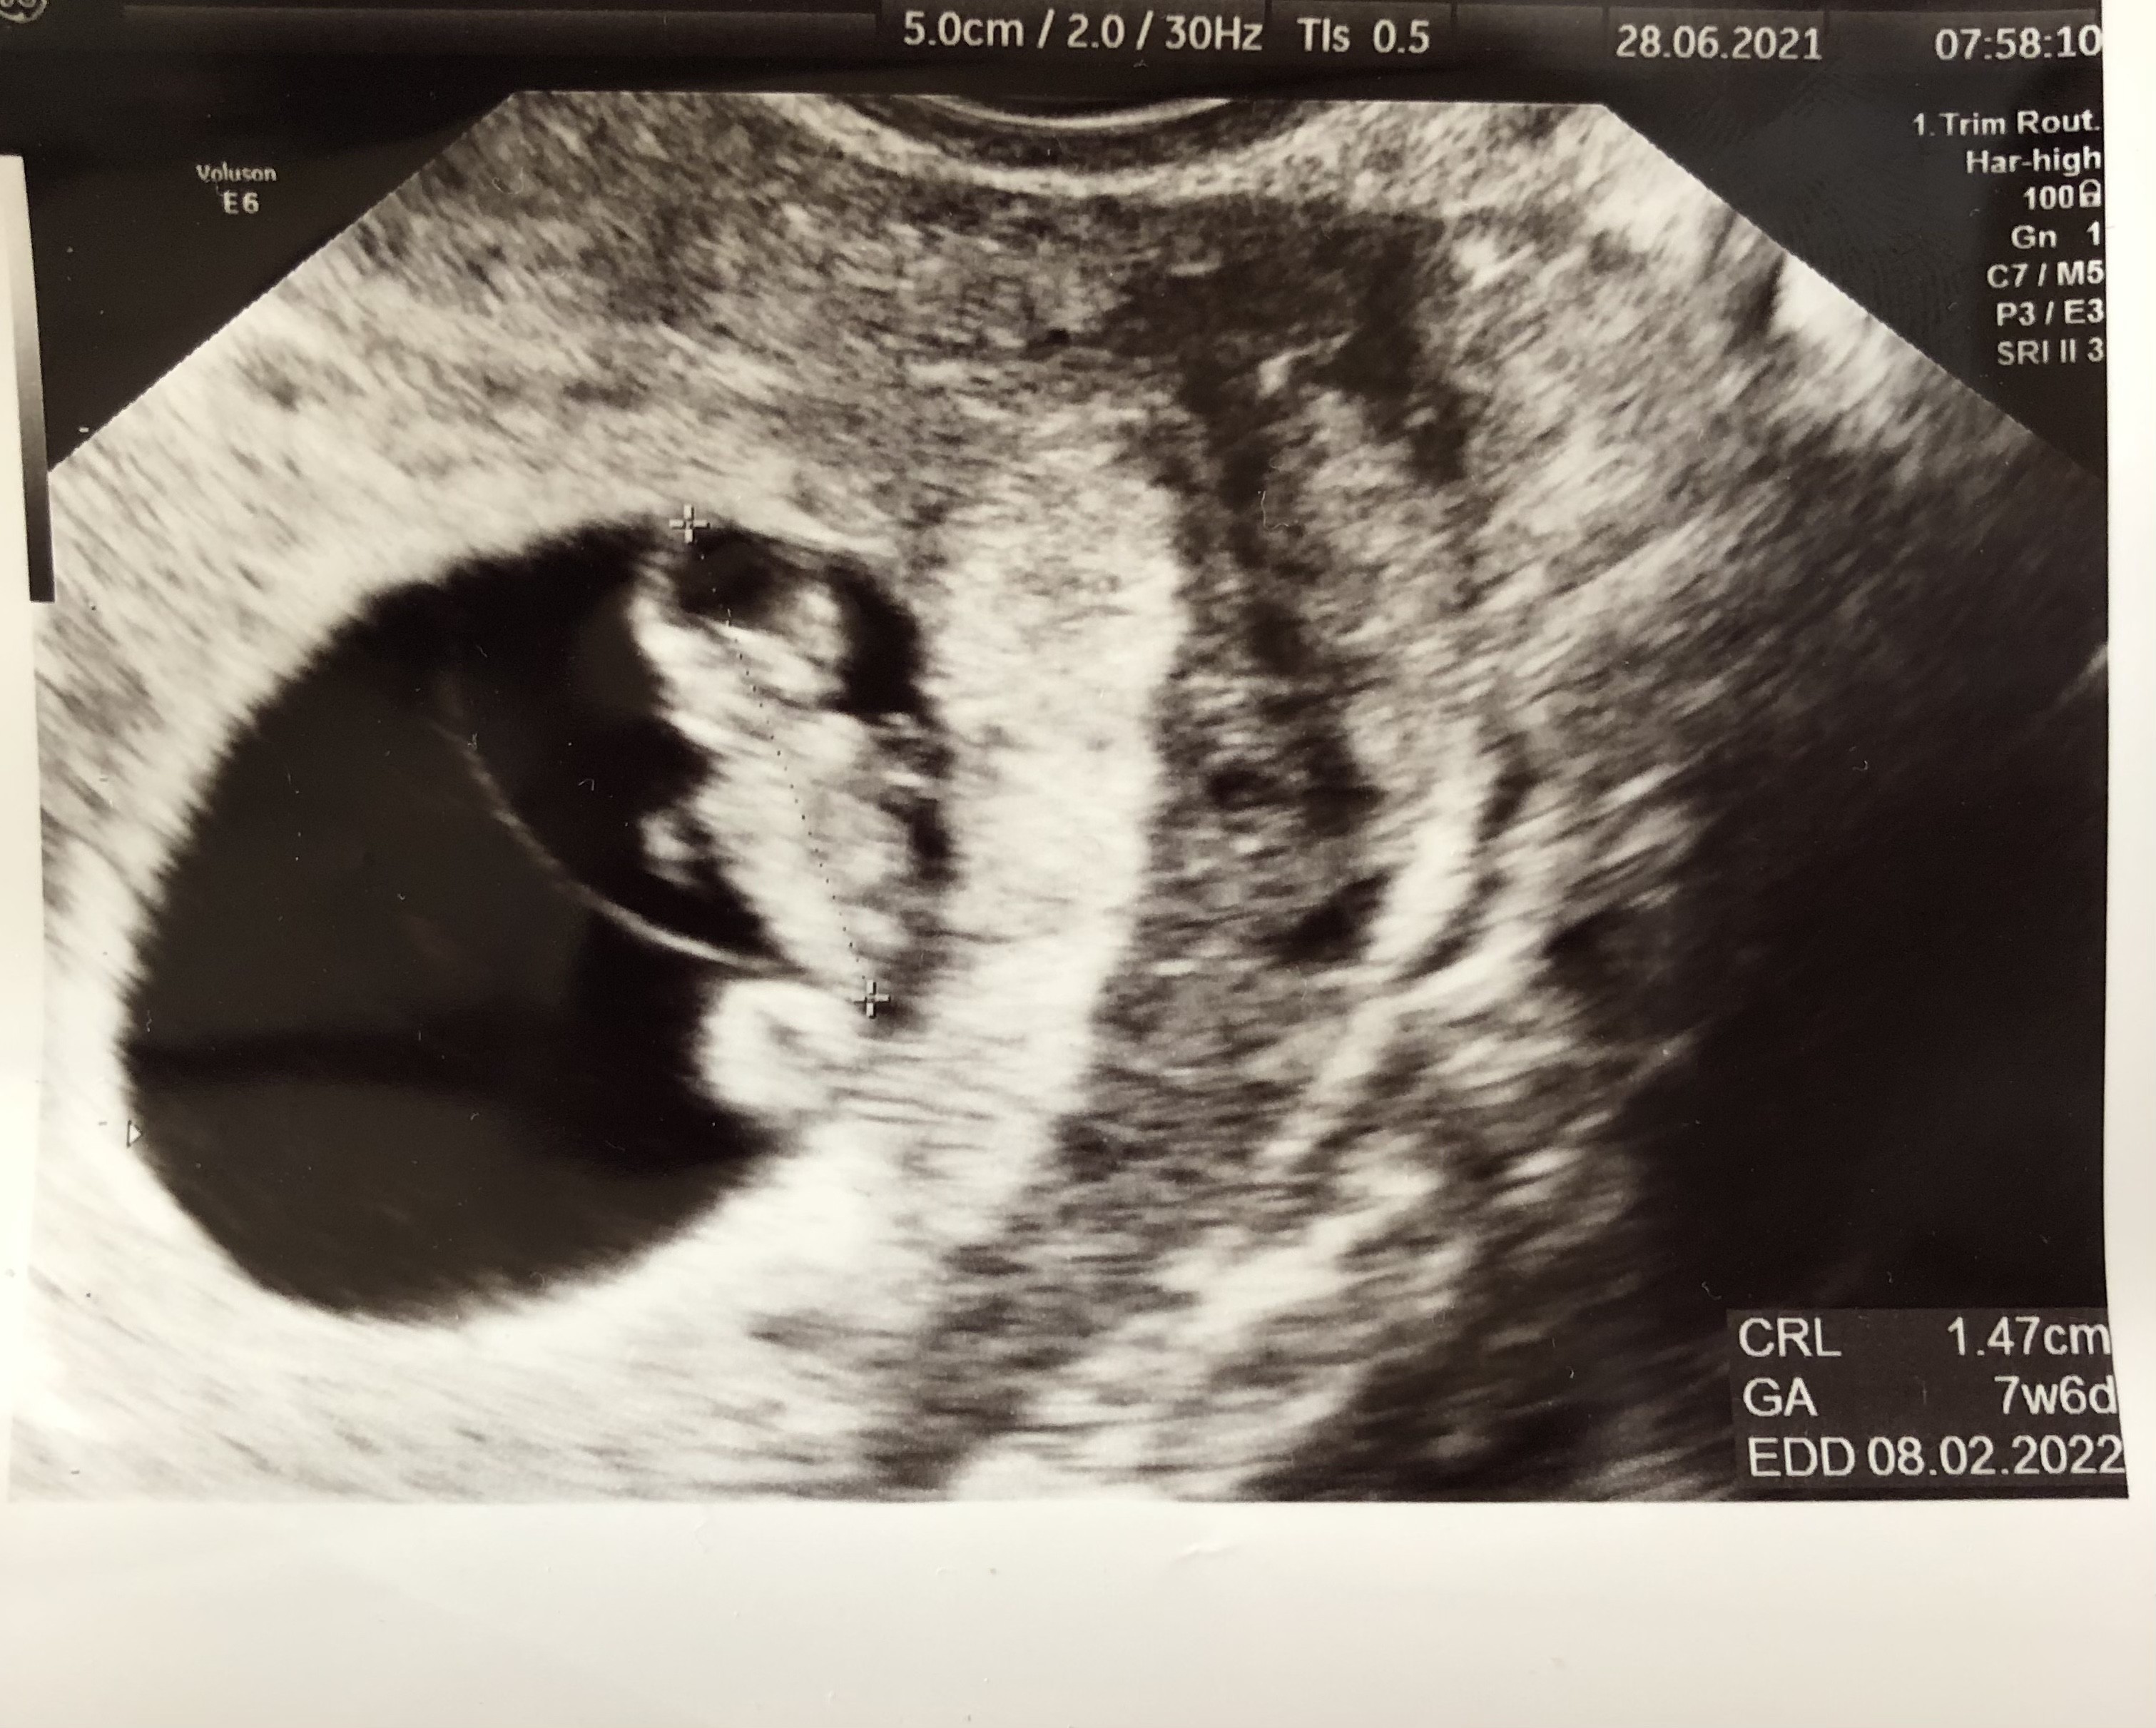

Dlatego teraz byłam gdzie indziej, u cudownej pani doktór którą też ma podejrzenie pustego jaja niestety ale nie przekreśliła mnie z góry , po prostu powiedziała żebym się nie stresowała może późno fasolka kiełkuje i na następnej wizycie ja zobaczymy wraz z serduchem

kazała powtórzyć bthcg ale doszłam do wniosku że nie robię , będzie to dla mnie dodatkowy stres, więc po prostu na spokojnie czekam do piątku